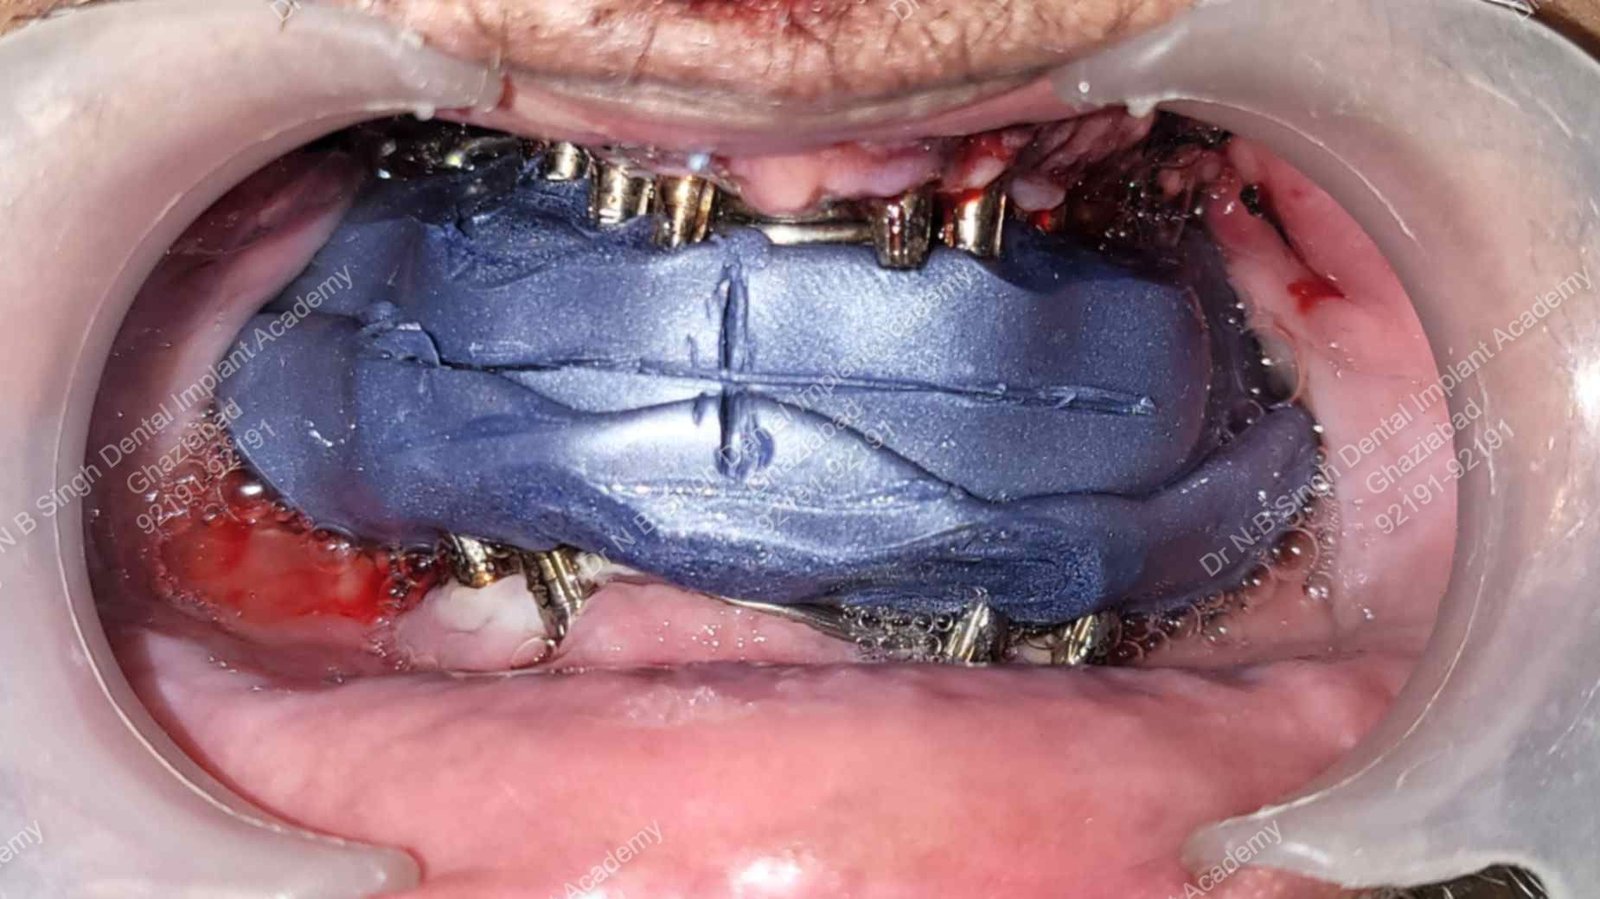

A009 Centric bite registration